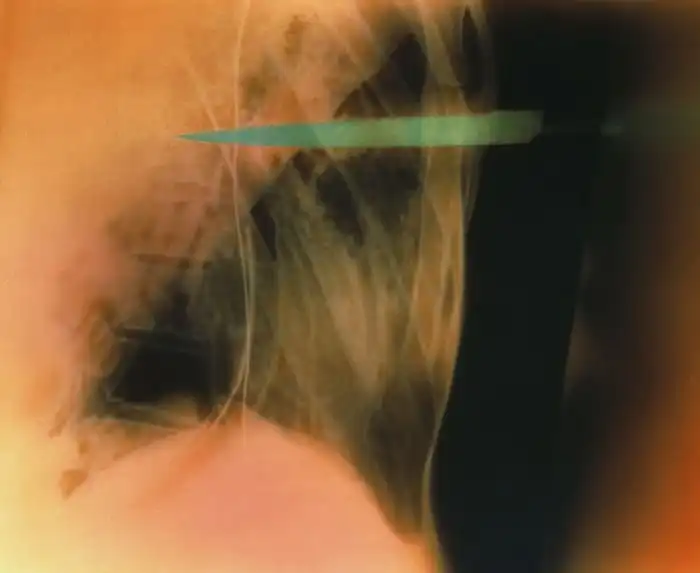

Жуткие рентгеновские снимки

Порой даже не верится, с какими странными и необычными повреждениями в травматологию могут поступить пострадавшие. Всю эпичность профессии врачей травматологии могут с легкостью подтвердить рентгеновские снимки.